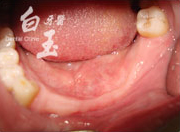

治療後